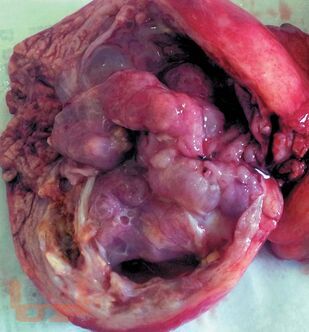

В руководстве приведен анализ и систематизирован опыт Института хирургии им. А.В. Вишневского и зарубежных авторов по вопросам диагностики и хирургического лечения кистозных опухолей поджелудочной железы. Описаны клинические проявления и анамнестические данные, характерные для таких пациентов. Дана ультразвуковая, компьютерно-томографическая, магнитно-резонансно-томографическая и эндоультразвуковая семиотика кистозных опухолей. Показаны возможности пункционной диагностики с исследованием цитологического состава кистозных опухолей и определением уровня онкомаркеров в их содержимом.

Описаны характерные морфологические признаки, приведены сведения о микроскопических и гистохимических маркерах различных вариантов кистозных опухолей, позволяющих определить их происхождение и прогнозировать дальнейшее течение. Отдельная глава посвящена дифференциальной диагностике кистозных опухолей с другими кистозными и опухолевыми поражениями поджелудочной железы.

Большое внимание уделено выбору оптимальной лечебной тактики. Подробно рассмотрены вопросы хирургического лечения кистозных опухолей в зависимости от их локализации в поджелудочной железе и морфологической структуры. Отражены вопросы комбинированного лечения злокачественных кистозных опухолей, а также ближайшие и отдаленные результаты лечения.